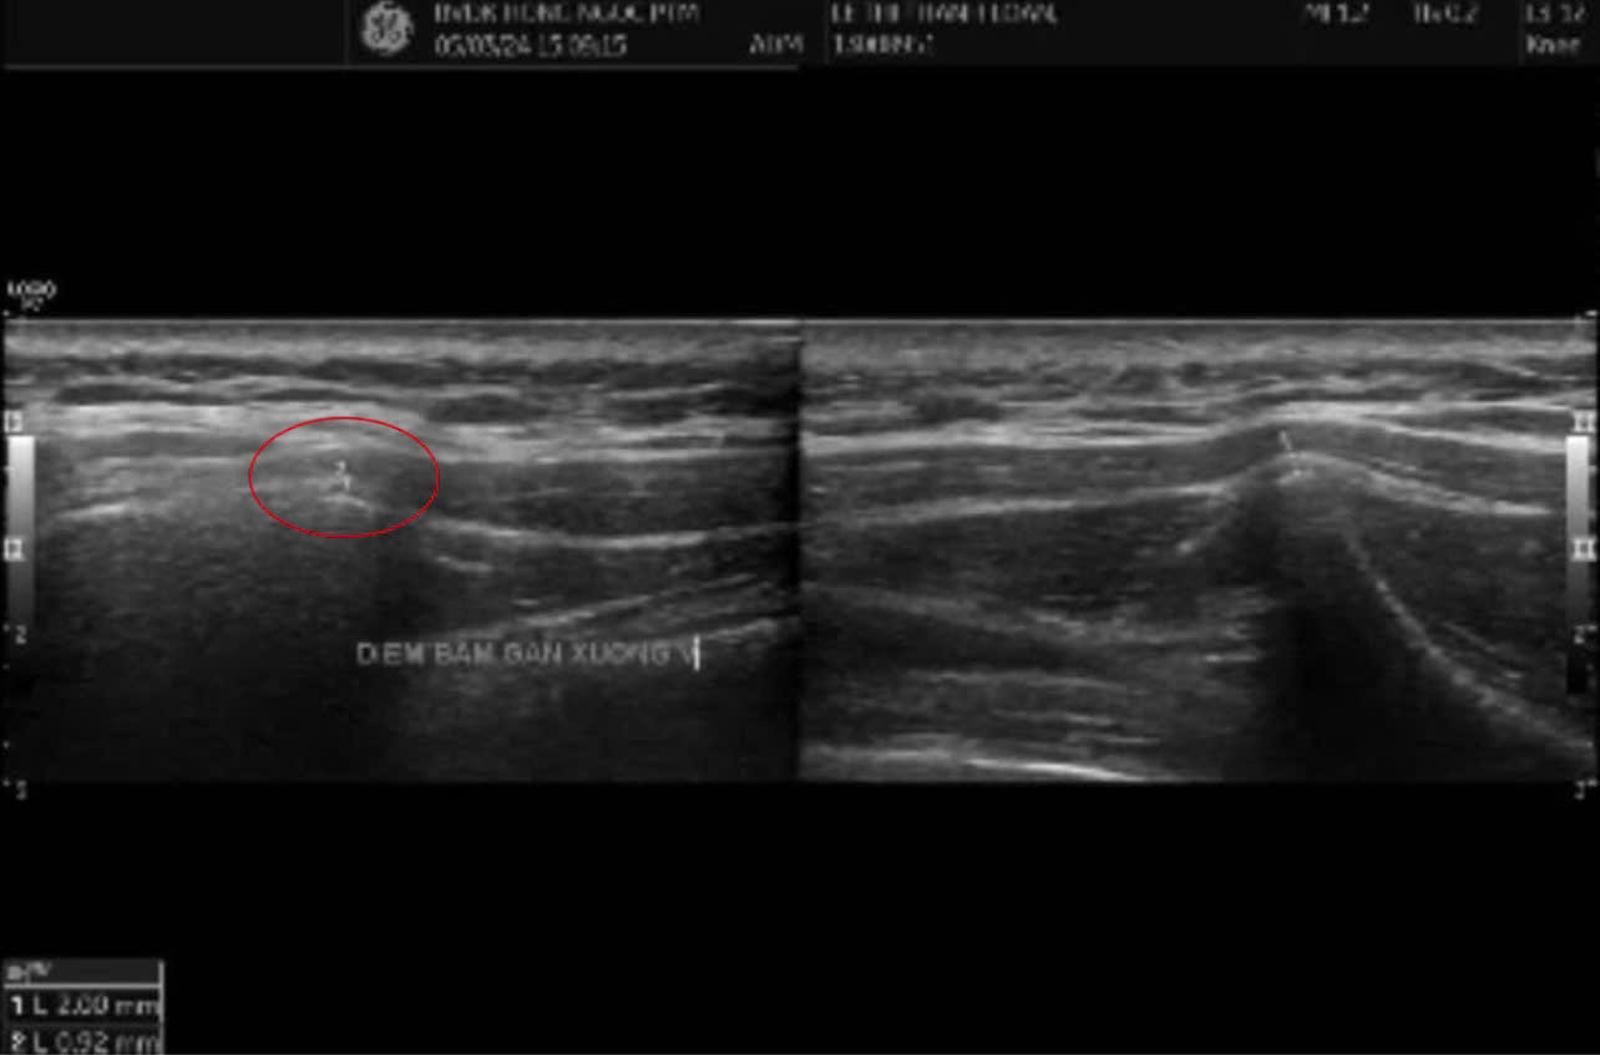

Sau khi nhận chẩn đoán “viêm điểm bám gân xương bả vai”, chị L được ThS.BS Trần Thị Kim Chuẩn (Khoa Cơ xương khớp - Bệnh viện Hồng Ngọc) giải thích chi tiết về tình trạng của mình. Bác sĩ Chuẩn nhấn mạnh: “Cơn đau bả vai có thể do nhiều nguyên nhân như thoái hóa, thoát vị đĩa đệm cột sống cổ hay hội chứng cổ vai tay, nên việc chẩn đoán sai khá phổ biến. Sau khi xem xét bệnh sử và thăm khám kỹ, bác sĩ phát hiện cơn đau tập trung tại điểm bám gân, với cảm giác đau nhói khi ấn vào – dấu hiệu điển hình của viêm gân. Kết quả siêu âm cho thấy gân bả vai phải dày hơn bình thường và bị viêm, xác định nguyên nhân chính gây ra cơn đau dai dẳng của chị L là viêm gân bám vào xương bả vai, điều mà trước đây chưa ai phát hiện".

Kết quả siêu âm cho thấy gân bả vai phải dày hơn và có dấu hiệu viêm so với bên còn lại

Ca bệnh của chị L cho thấy, ngoài thăm khám lâm sàng kỹ lưỡng, việc kết hợp chẩn đoán hình ảnh như siêu âm là cần thiết, giúp bác sĩ đánh giá rõ ràng hơn tình trạng bệnh và đưa ra phương pháp điều trị phù hợp.